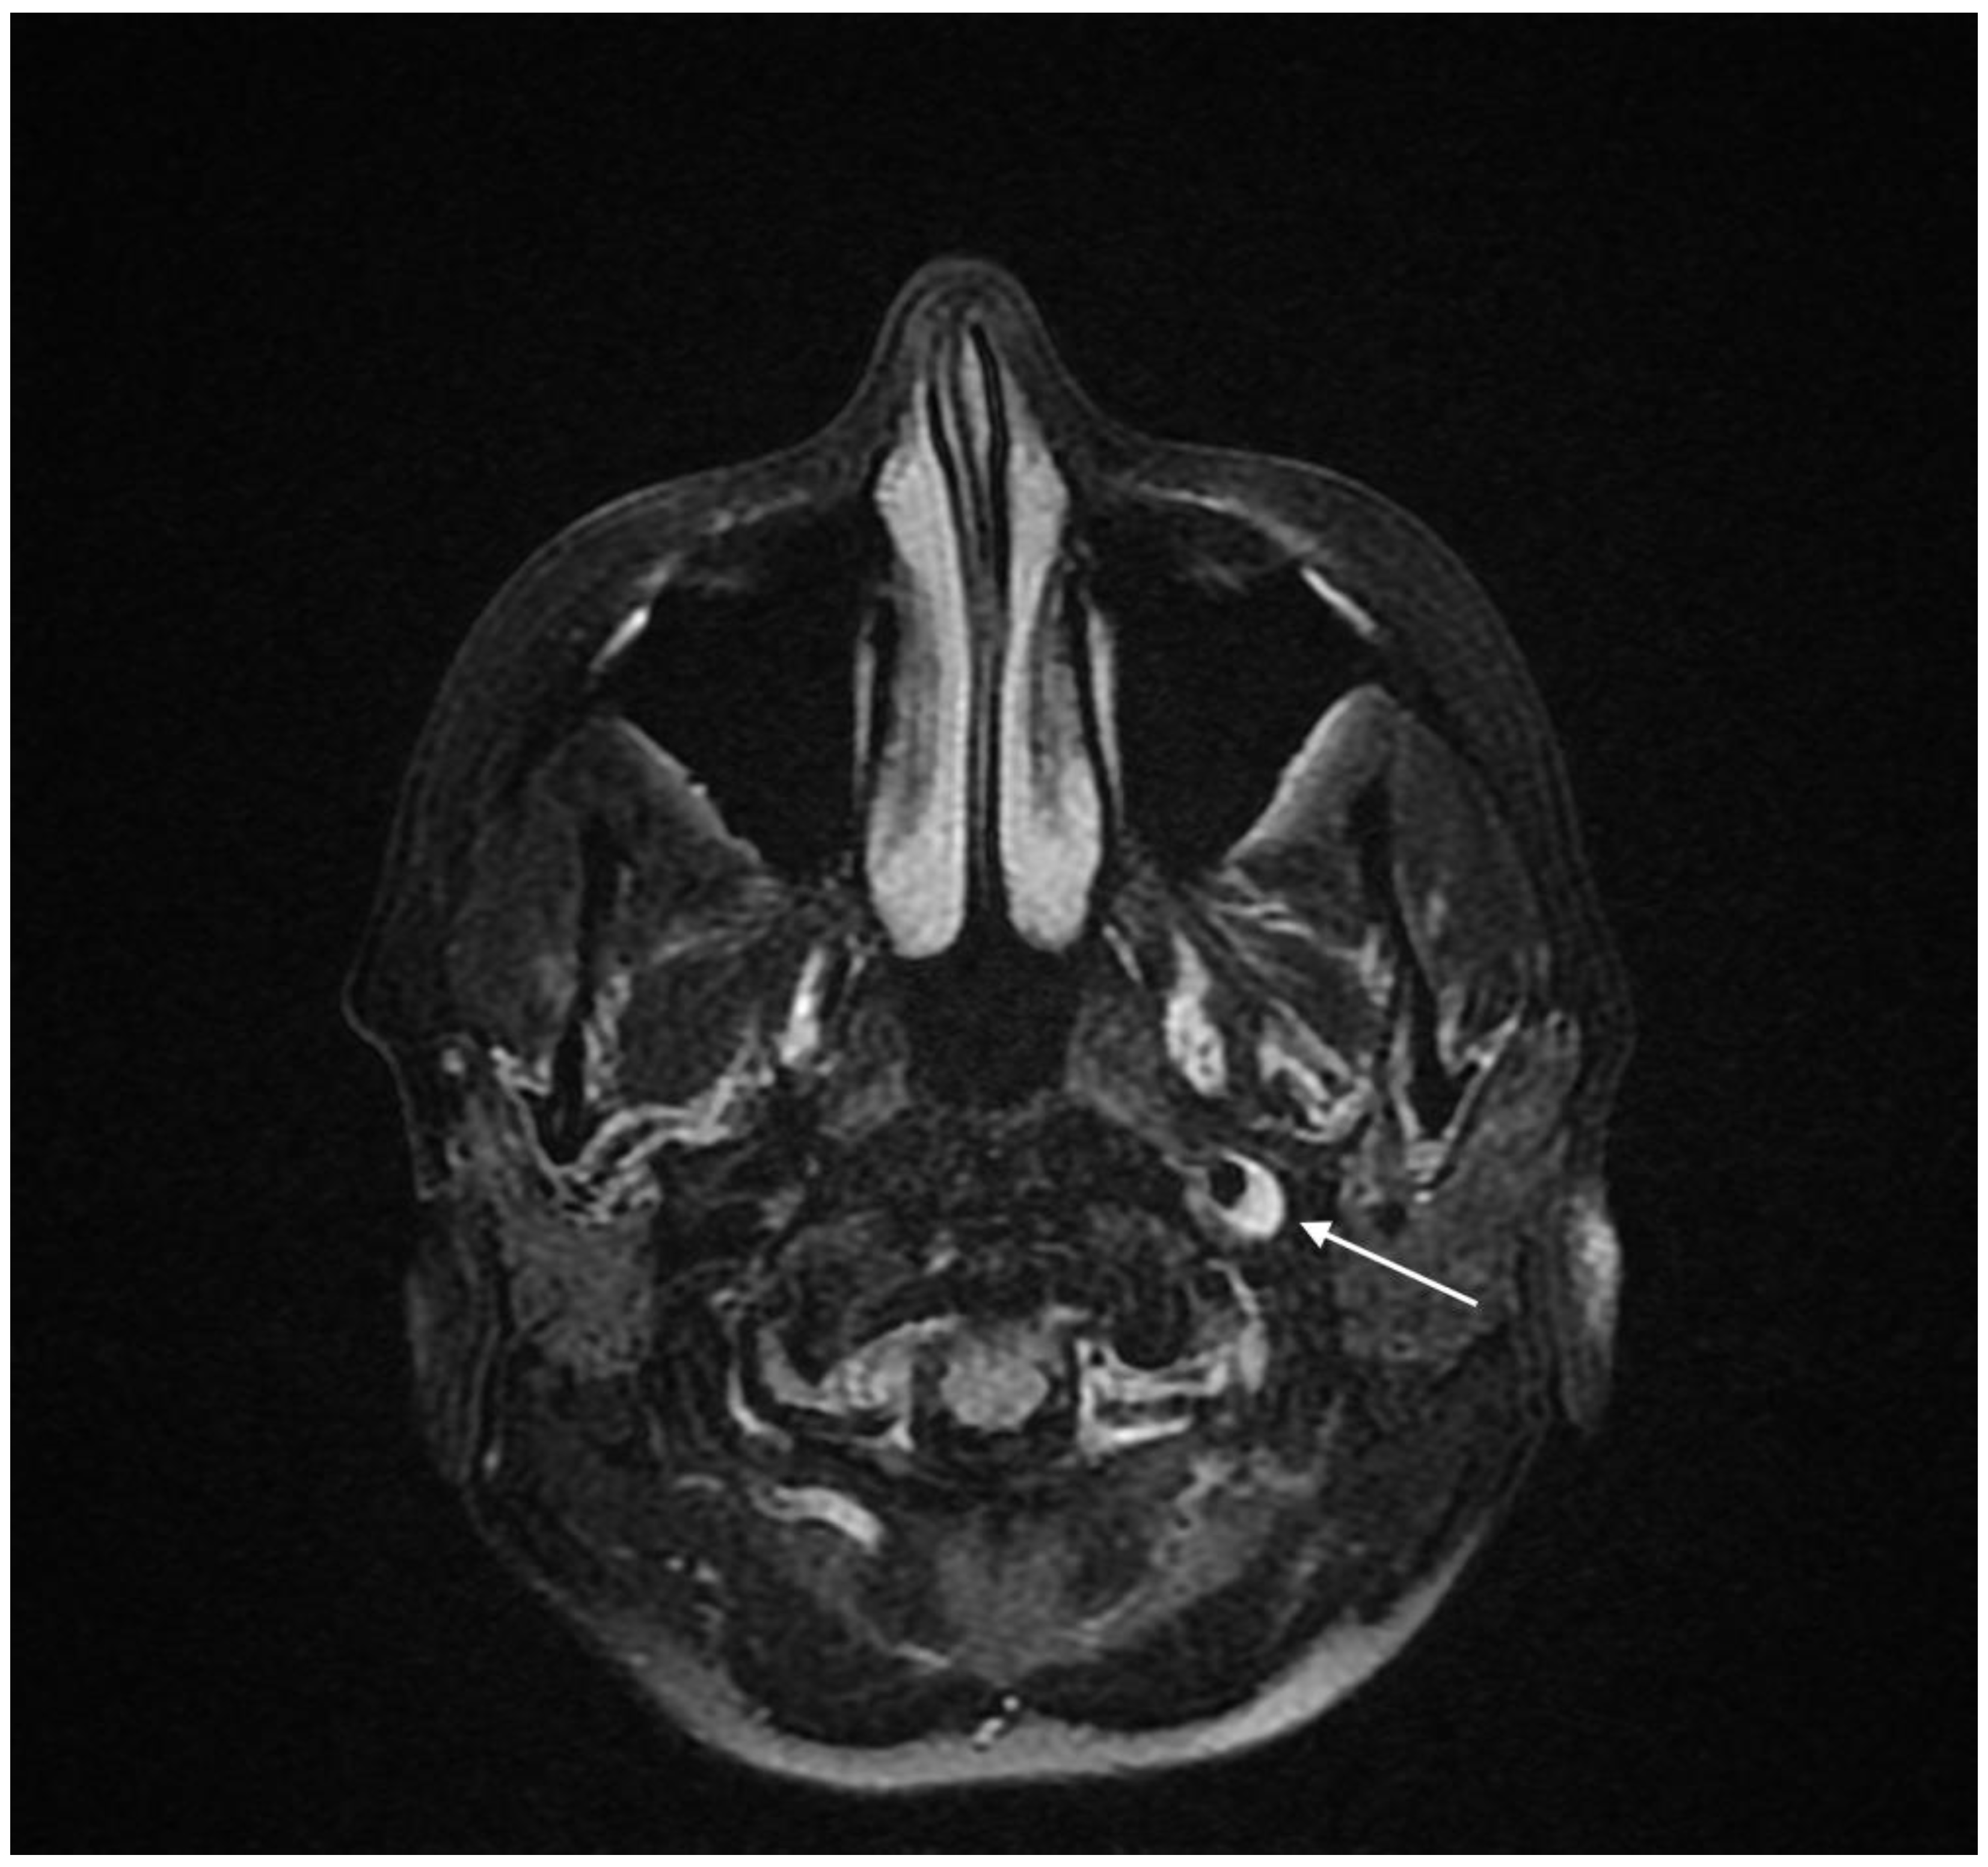

2. Case Presentation

2.2. Diagnosis